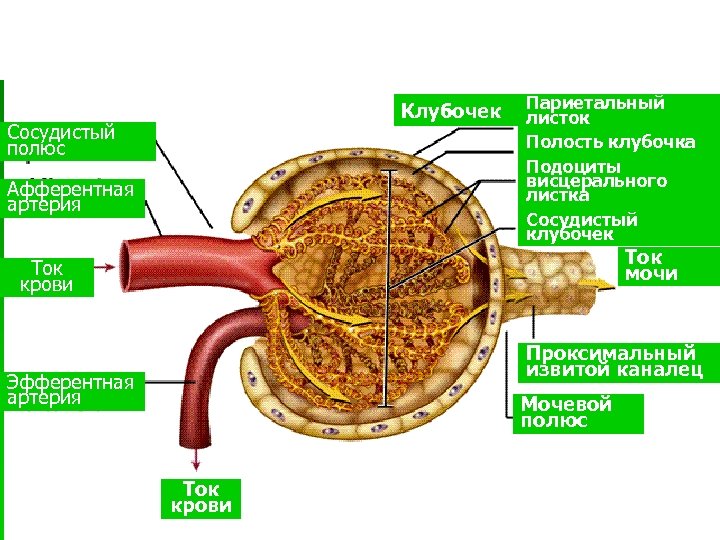

Клубочек Сосудистый полюс Афферентная артерия Париетальный листок Полость клубочка Подоциты висцерального листка Сосудистый клубочек Ток мочи Ток крови Проксимальный извитой каналец Эфферентная артерия Мочевой полюс Ток крови